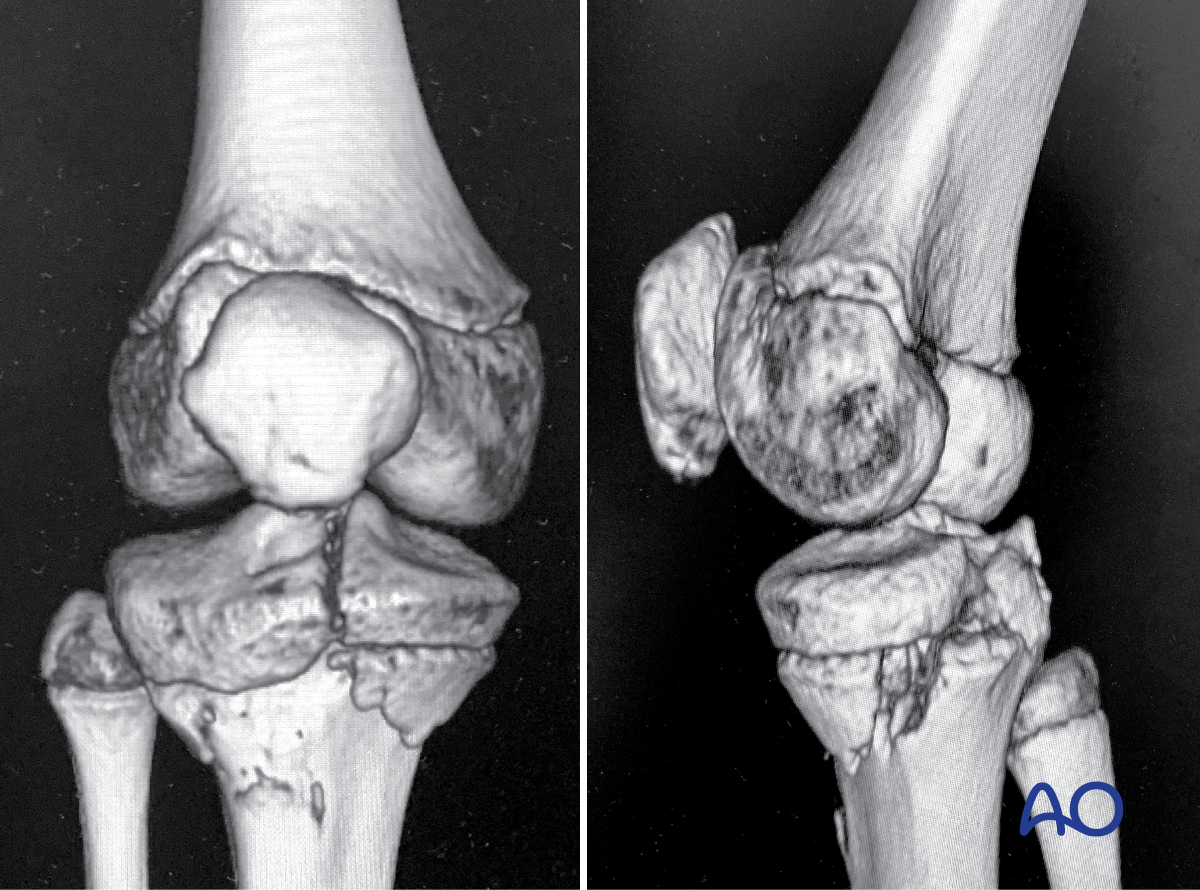

This module includes a detailed consideration of all patterns of physeal injury using a spectrum of techniques. A description of bridge plating has also been introduced, which is relevant to the older child in addition to specialist techniques, which combine conventional osteosynthesis with arthroscopy to manage intraarticular fractures.

- Salter-Harris type-I–IV fractures

This includes detailed procedures on K-wire and screw fixation, external fixation, plate fixation, in addition to nonoperative management with casting and splinting.